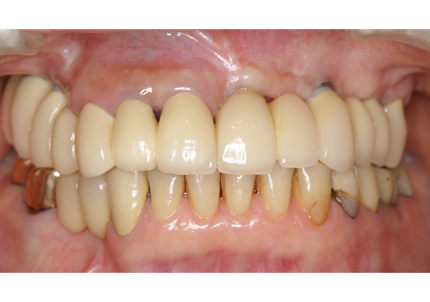

1.初診時(2015年6月)

2.最終補填物装着(2018年3月)

3.術後8年経過(2023年3月)

術後8年経過良好

2015年6月初診時レントゲン

2023年3月レントゲン 経過良好